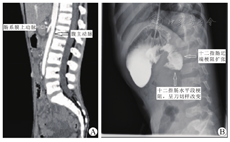

回顾性分析2015年1月至2018年1月华中科技大学同济医学院附属武汉儿童医院普外科手术治疗肠系膜上动脉综合征患儿4例,其中男1例,女3例,年龄6~12岁,平均年龄8岁,入院时平均体重22.25 kg,平均身体质量指数14.2 kg/m2,呈瘦长体型,均以急性起病,病程较短,平均病程1个月,临床症状均以呕吐及腹痛为主,多在进食后呕吐,呕吐物为胆汁样物。腹痛部位多为脐周为主,呈间断性发作,其中1例表现为胸膝位可缓解,其他3例无明确资料可以证实。患儿多合并有水电解质紊乱(3例)及营养不良(4例)。体检主要表现为上腹部或脐周的压痛,上腹部饱满及逆蠕动波在患儿中并不常见。术前均行腹部CT、消化道造影及胃镜检查以明确诊断。腹部CT检查均提示肠系膜上动脉及腹主动脉夹角变小,分别为11°、10°、14°及16°,平均13°(图1A)。肠系膜上动脉到腹主动脉距离缩小,分解为6 mm、7 mm、8 mm及5 mm,平均7 mm。消化道造影提示十二指肠水平段的梗阻,呈刀切样或笔杆样表现,近段十二指肠明显扩张(图1B)。胃镜检查无特异性发现,主要表现为胃或十二指肠的慢性糜烂或溃疡,胃镜主要用于排除十二指肠膜式狭窄,并可以必要时放置空肠营养管给予肠内营养治疗。